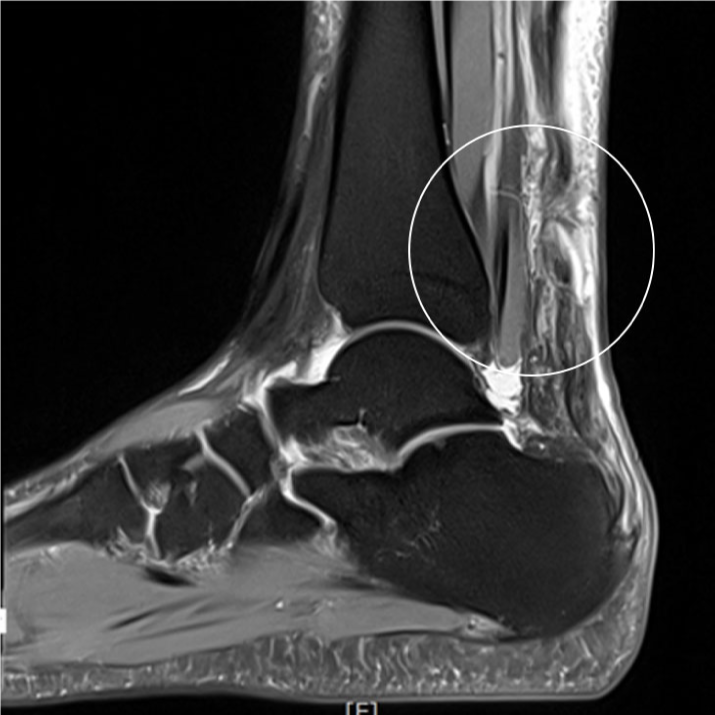

아킬레스건 파열 봉합술 전후 아킬레스건 근전 접합부 완전 파열 및 동반된 종파열

• ㆍ수술 30분~1시간

• ㆍ입원 3~4일

• ㆍ4주간 깁스 착용

• ㆍ보조기 착용